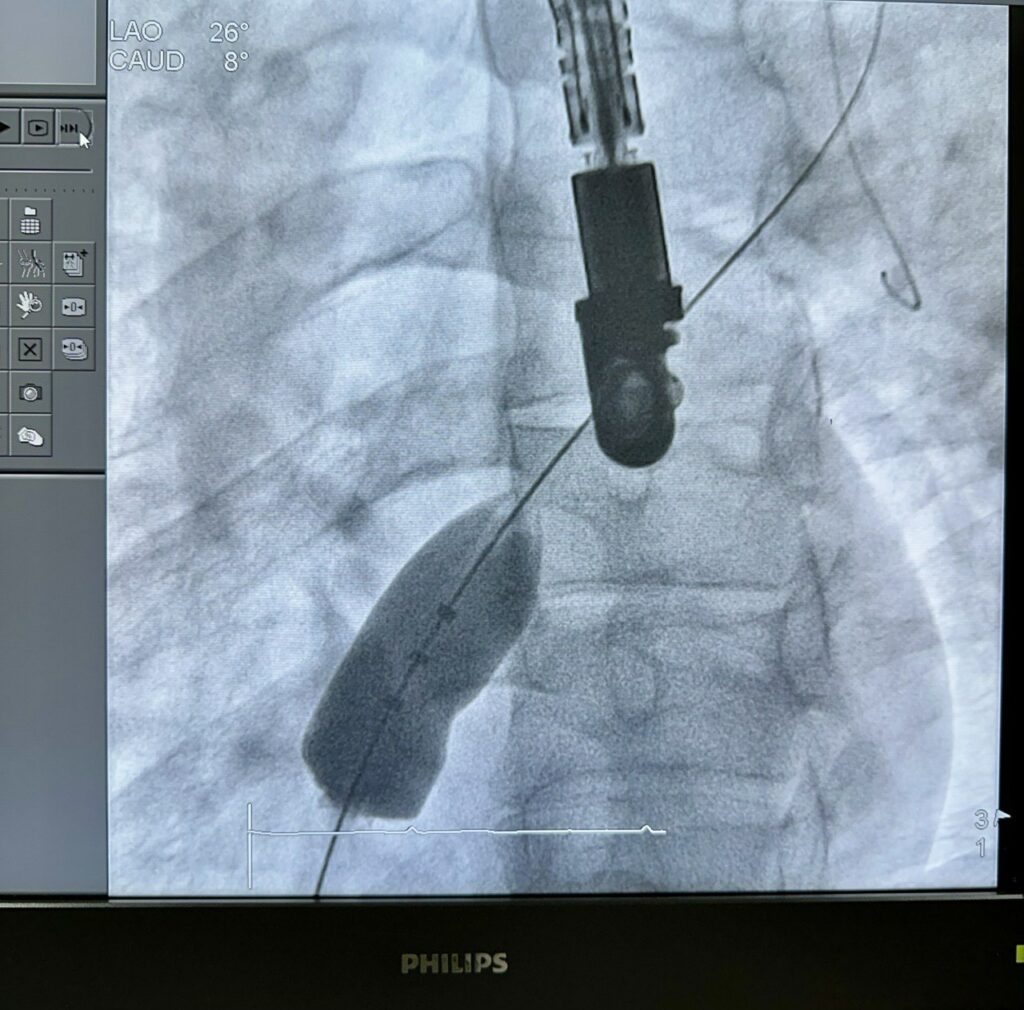

Сучасні технології дозволяють усунути валу малоінвазивним ендоваскулярним методом – без великих розрізів, зупинки серця та застосування штучного кровообігу. У судину вводять спеціальний пристрій – оклюдер, що нагадує мініатюрну парасольку. Він виготовлений зі спеціального сплаву, має властивість пам’яті форми і закриває дефект, відновлюючи нормальний кровотік.

Для точного позиціонування оклюдера та контролю його розкриття використовують комплексне поєднання візуальних методів. Кардіохірурги одночасно орієнтуються на зображення з ангіографа та трансстравохідного УЗД, що дає змогу в режимі реального часу оцінити правильність установки імпланта, його стабільність і повне закриття дефекту.